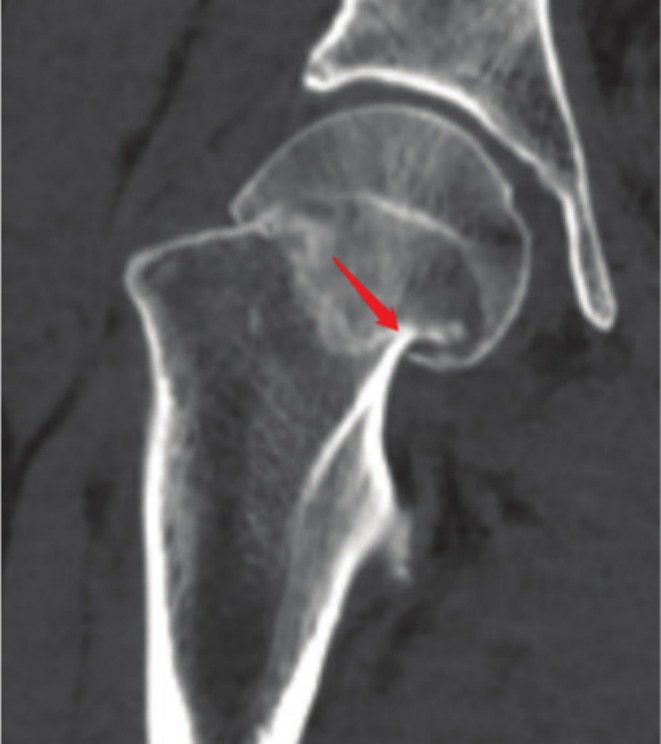

Methods: A retrospective analysis was conducted on 350 femoral neck fracture patients (aged 18-65 years) treated with closed reduction and three cannulated screws fixation at a single institution from 2015 to 2020. Evaluate the clinical and imaging information of patients such as sex, age, body mass index, Garden classification, calcar femorale injury situation, computed tomography Hounsfield units (CT HUs), comorbidities (e.g., diabetes, hypertension etc.) and complications (femoral neck shortening, nonunion, and femoral head necrosis). CT-based 3D reconstruction was used to analyze calcar femorale morphology. Statistical analyses included univariate and multivariate logistic regression to identify independent risk factors.